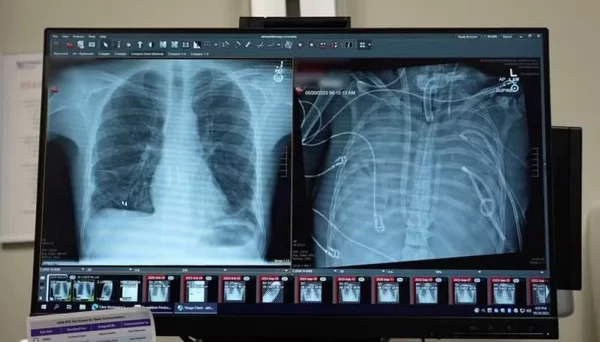

Os médicos retiraram os dois pulmões e instalaram o dispositivo, que oxigenava o sangue, removia o dióxido de carbono e mantinha o fluxo sanguíneo necessário para o coração e o restante do corpo, permitindo que o paciente permanecesse vivo enquanto se recuperava da infecção sistêmica.

O resultado surpreendeu a equipe médica. Assim que os pulmões foram removidos, o homem começou a apresentar melhora. A pressão arterial se estabilizou, outros órgãos passaram a funcionar melhor e a infecção cedeu.

Em dois dias, o quadro clínico mudou completamente, e ele pôde receber o transplante. Hoje, cerca de dois anos após o procedimento, leva uma vida normal.